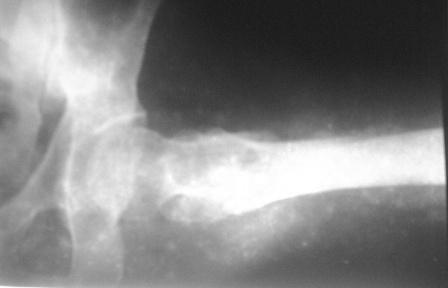

Больному 50л. В отдаленном от центра р-не ДТП 6.12.08г. д-з " тяжелая

ЧМТ, мн. переломы ребер слева, отрыв ножки селезенки, повреждение п/ж

железы, з/двойной перелом прав. бедра.После экстрен. хирургических

вмешательств, конечность фиксирован кокситной гипсовой лонгетной

повязкой. Кома 2 нед, нагноение п/о раны живота, постравмат.

пневмония.

20.01.09г. переведен к нам. Постельный больной,

ослабленный, бледный, весом 56кг:  свищ п/о раны перед.брюшной стенки

с сукровичным выделением, гипс снят - деформация и укорочение

бедра на 6см, в обл перелома есть спайка. Слабо, но активно поднимает

ногу, контрактура т/б и коленных суставов.

Наш план блокир. и/м остеосинтез. Имеется гвозди для ВНПБ ЦИТО, но PFN не имеется.

-Можно ли остеосинтез гвоздем для высоких и низких переломов бедра?

-Если да,  как установить дистракцион. усстройство А.Н Челнокова?

- Может быть, еще какие-то нюансы имеется?

Вложение не в текстовом формате было извлечено…

Имя     : PICT0015.JPG

Тип     : image/jpeg

Размер  : 9373 байтов

Описание: отсутствует

Url     : http://weborto.net:8080/pipermail/ortho/attachments/20090125/3084e8b8/attachment-0005.jpeg